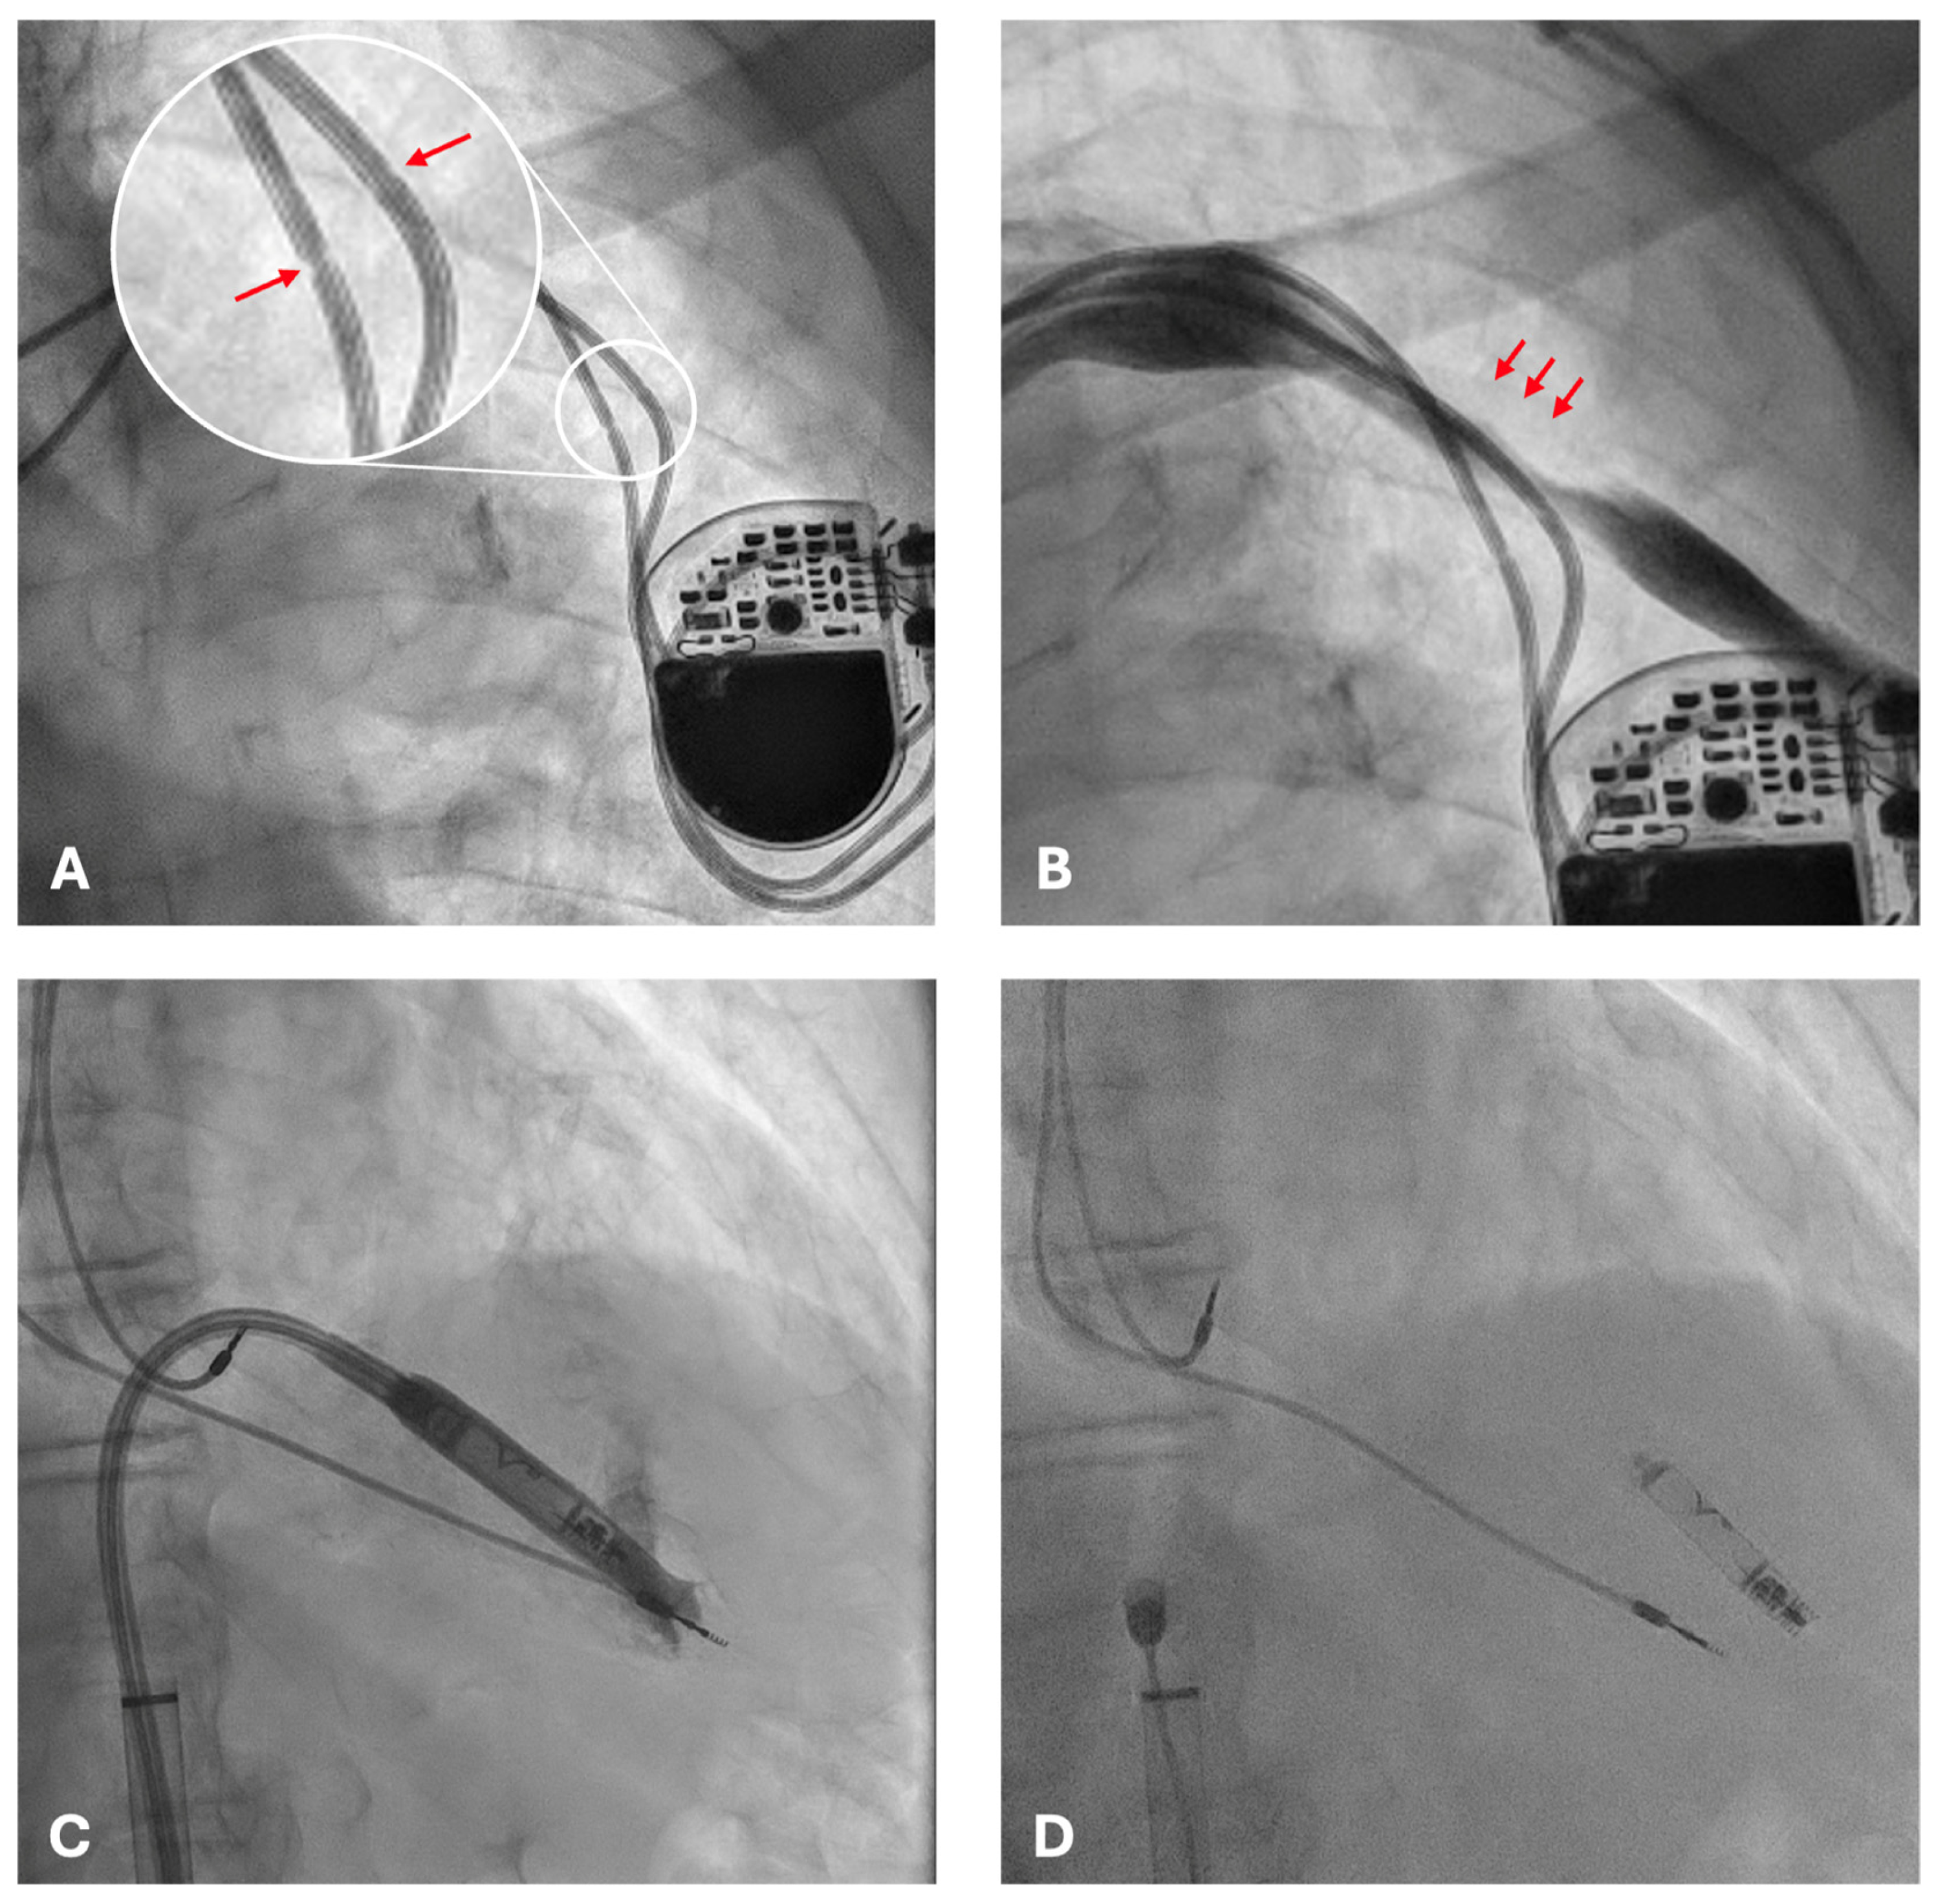

Fluoroscopic examination demonstrated the pacemaker generator in situ with both atrial and ventricular leads displaying focal narrowings in the infraclavicular region (Figure 2A). These findings were consistent with chronic mechanical damage, most likely related to suture fixation without protective sleeves at the time of implantation.

Conventional transvenous reimplantation was not feasible because of complete left subclavian vein occlusion (Figure 2B) and arterial overlap. Extraction of the damaged leads was deemed high risk. Leadless pacemaker implantation represented the only feasible and safe alternative, given the presence of complete venous occlusion, the high hemorrhagic risk of contralateral reimplantation, and the prohibitive risk of extraction. A leadless pacemaker (Aveir, Abbott, Abbott Park, IL, USA) was therefore selected as the optimal solution.

The procedure was performed via ultrasound-guided right femoral venous access without interruption of anticoagulation therapy. The presence of pre-existing intracardiac leads posed technical challenges, obstructing advancement of the delivery system (Figure 2C) and requiring multiple repositioning attempts. After careful manipulation and sheath angulation adjustments, stable fixation of the leadless device was achieved on the apico-septal region of the right ventricle (Figure 2D).

Figure 2. Fluoroscopic images during evaluation and intervention. (A) Dual-chamber pacemaker with atrial and ventricular leads in situ; arrows indicate focal narrowing of the leads near the clavicular region, consistent with mechanical compression injury from suture fixation without protective sleeves. (B) Distortion of the venous course with focal narrowing (arrows) along the left subclavian vein, consistent with complete left subclavian vein occlusion, which precluded new transvenous access. (C) Advancement of the leadless pacemaker delivery sheath into the right ventricle, with interference from pre-existing intracardiac leads. (D) Final stable deployment of the Aveir leadless pacemaker on the apico-septal region of the right ventricle, with satisfactory positioning and electrical performance despite the presence of abandoned leads.